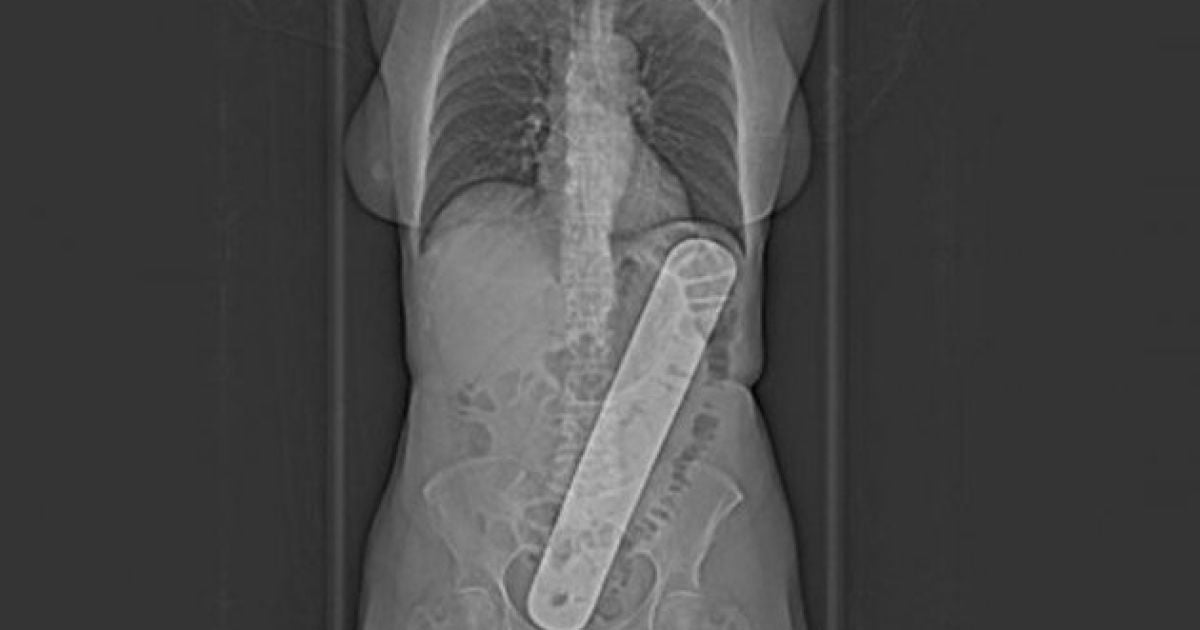

Хирурги одного из госпиталей Монреалю забыли в теле пациентки 30-сантиметровую металлическую пластину.

Пациентка Сильвия Дубе после прохождения операции на матке начала ощущать сильные боли в плече. Врачи долгое время пытались установить диагноз и даже начали лечить воспаление в плече. Но пізіше они сделали рентген брюшной полости, обнаружили в ней 30-сантиметровую пластину. Такая пластина используется для защиты желудка и внутренностей во время операции.